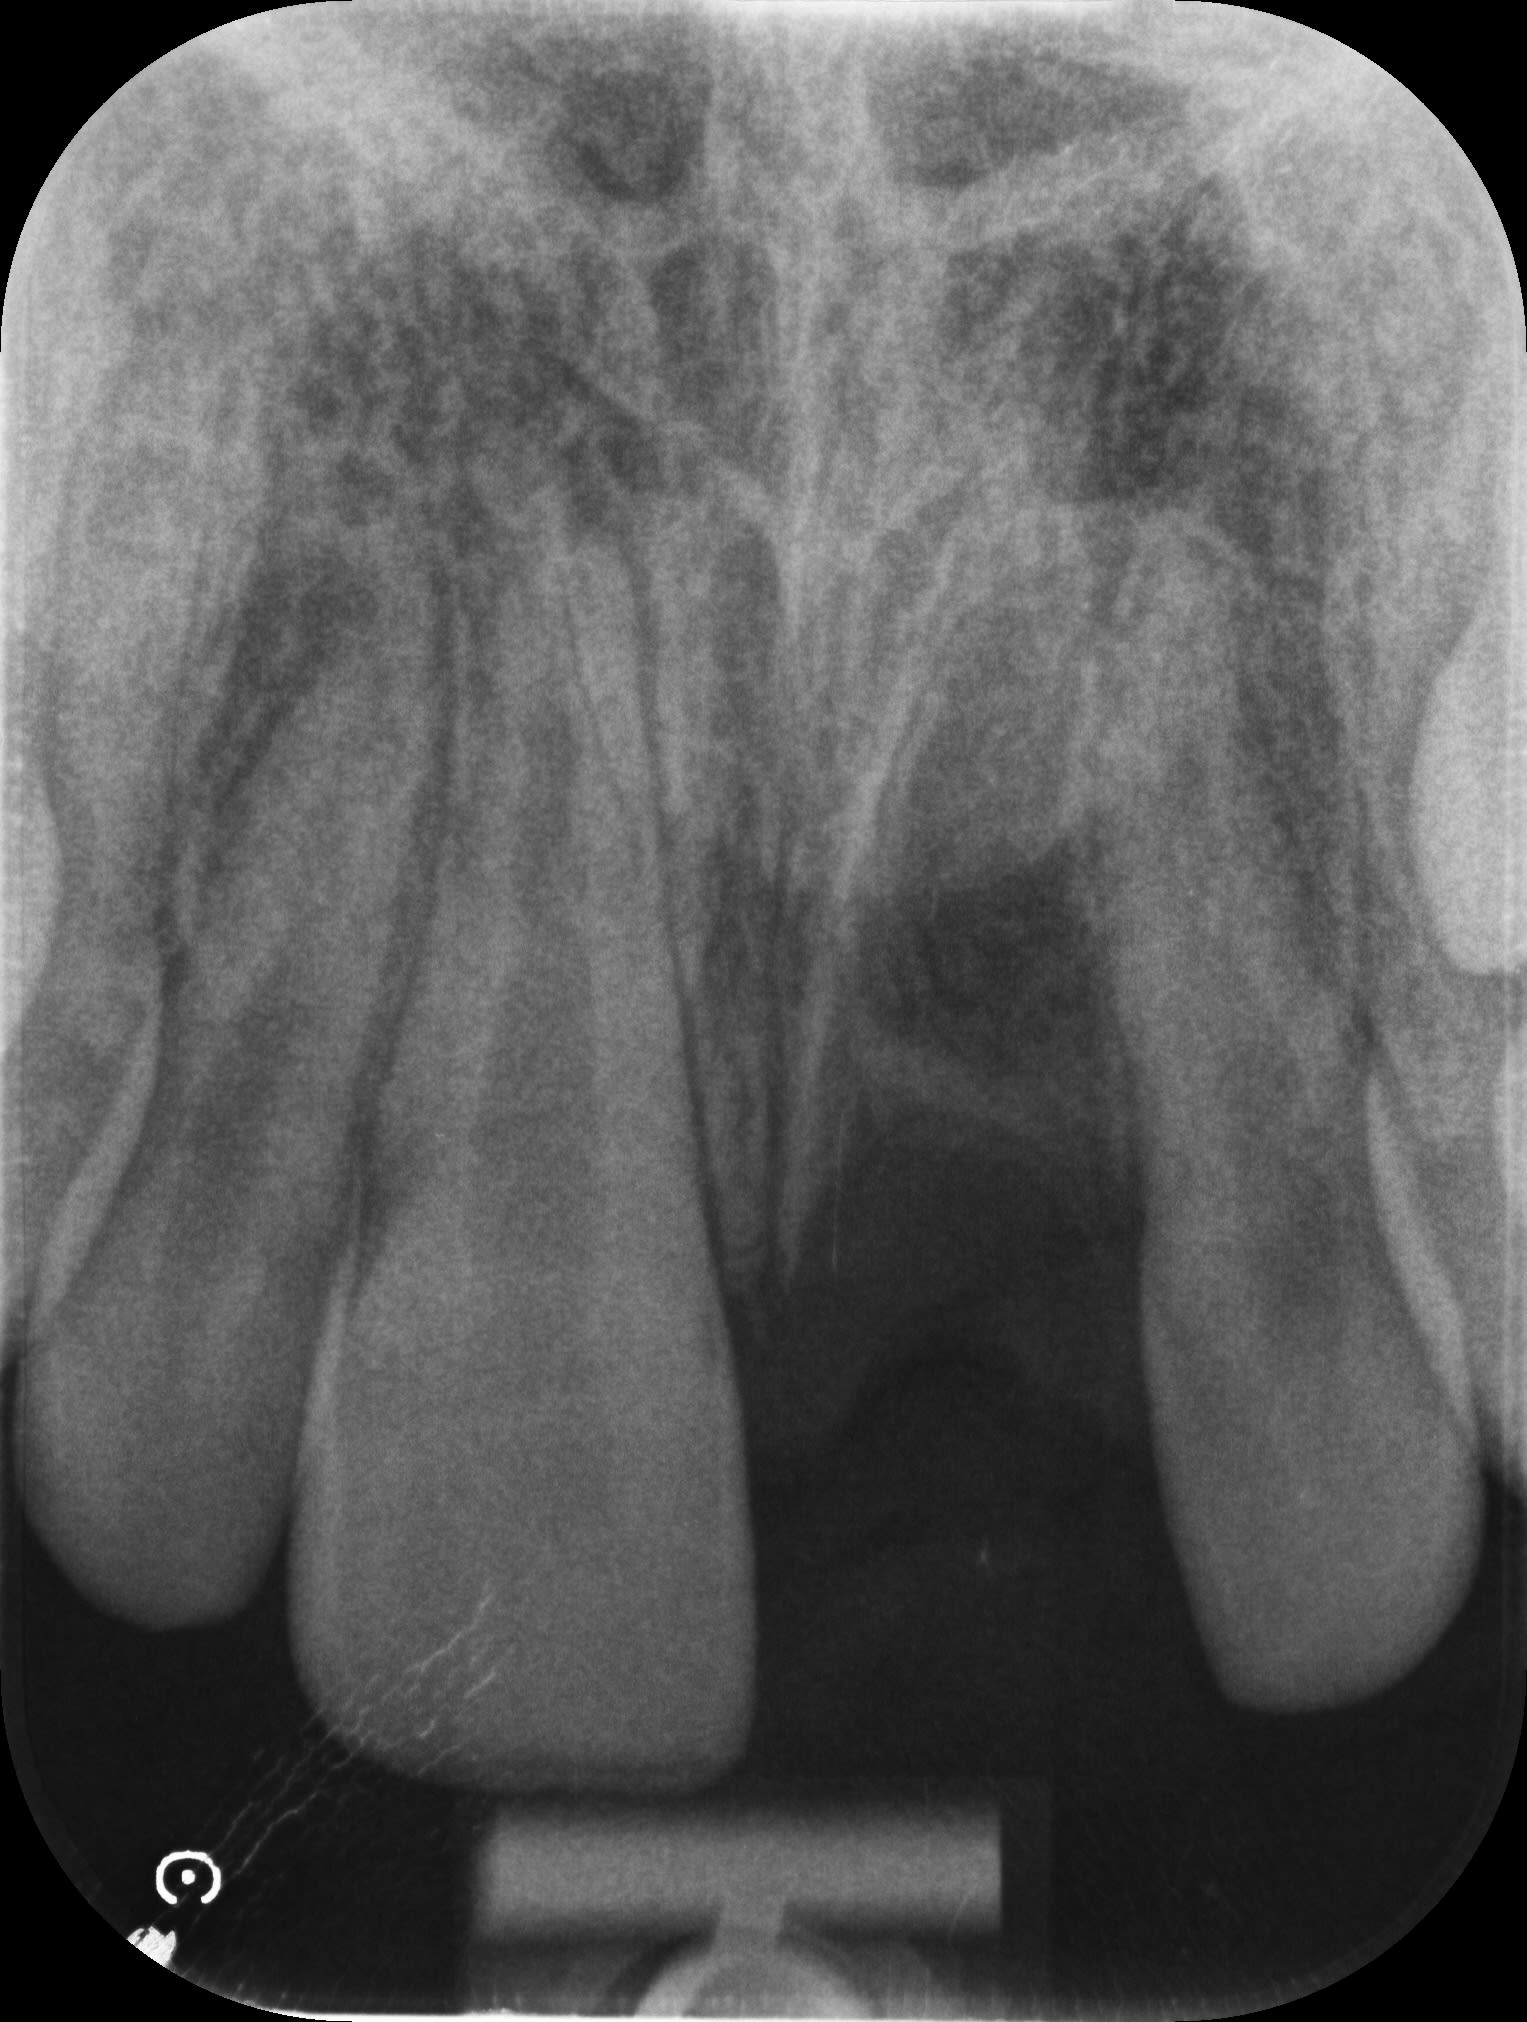

Petit cas clinique d'un traumatisme avec expulsion de 21 sur un enfant de 11 ans et 10 mois.

- 12/22 concussion - 11 subluxation - 21 expulsion

- radiographie apicale + OPT